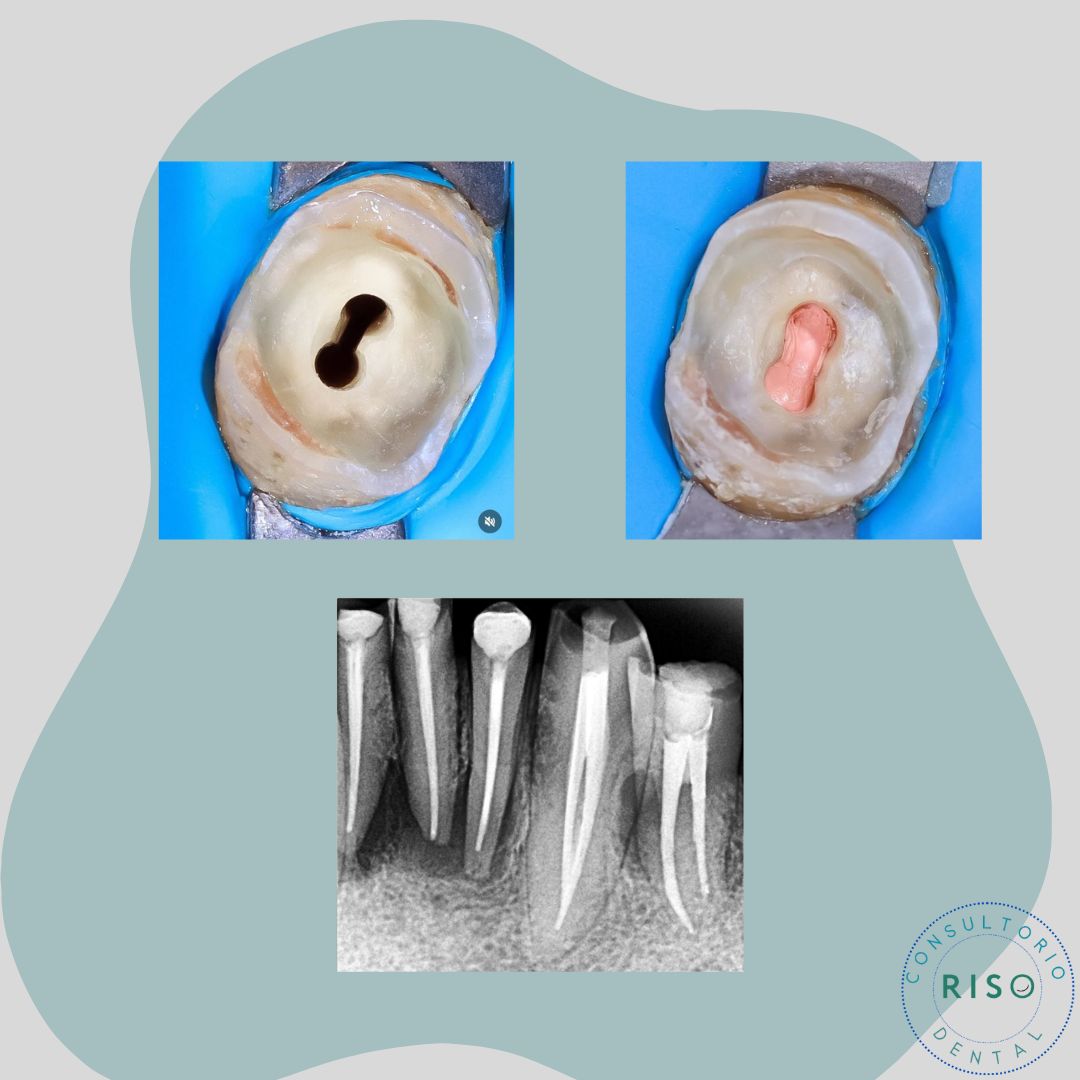

• Retratamiento de endodoncia

• Restauraciones Adhesivas o Incrustaciones dentales